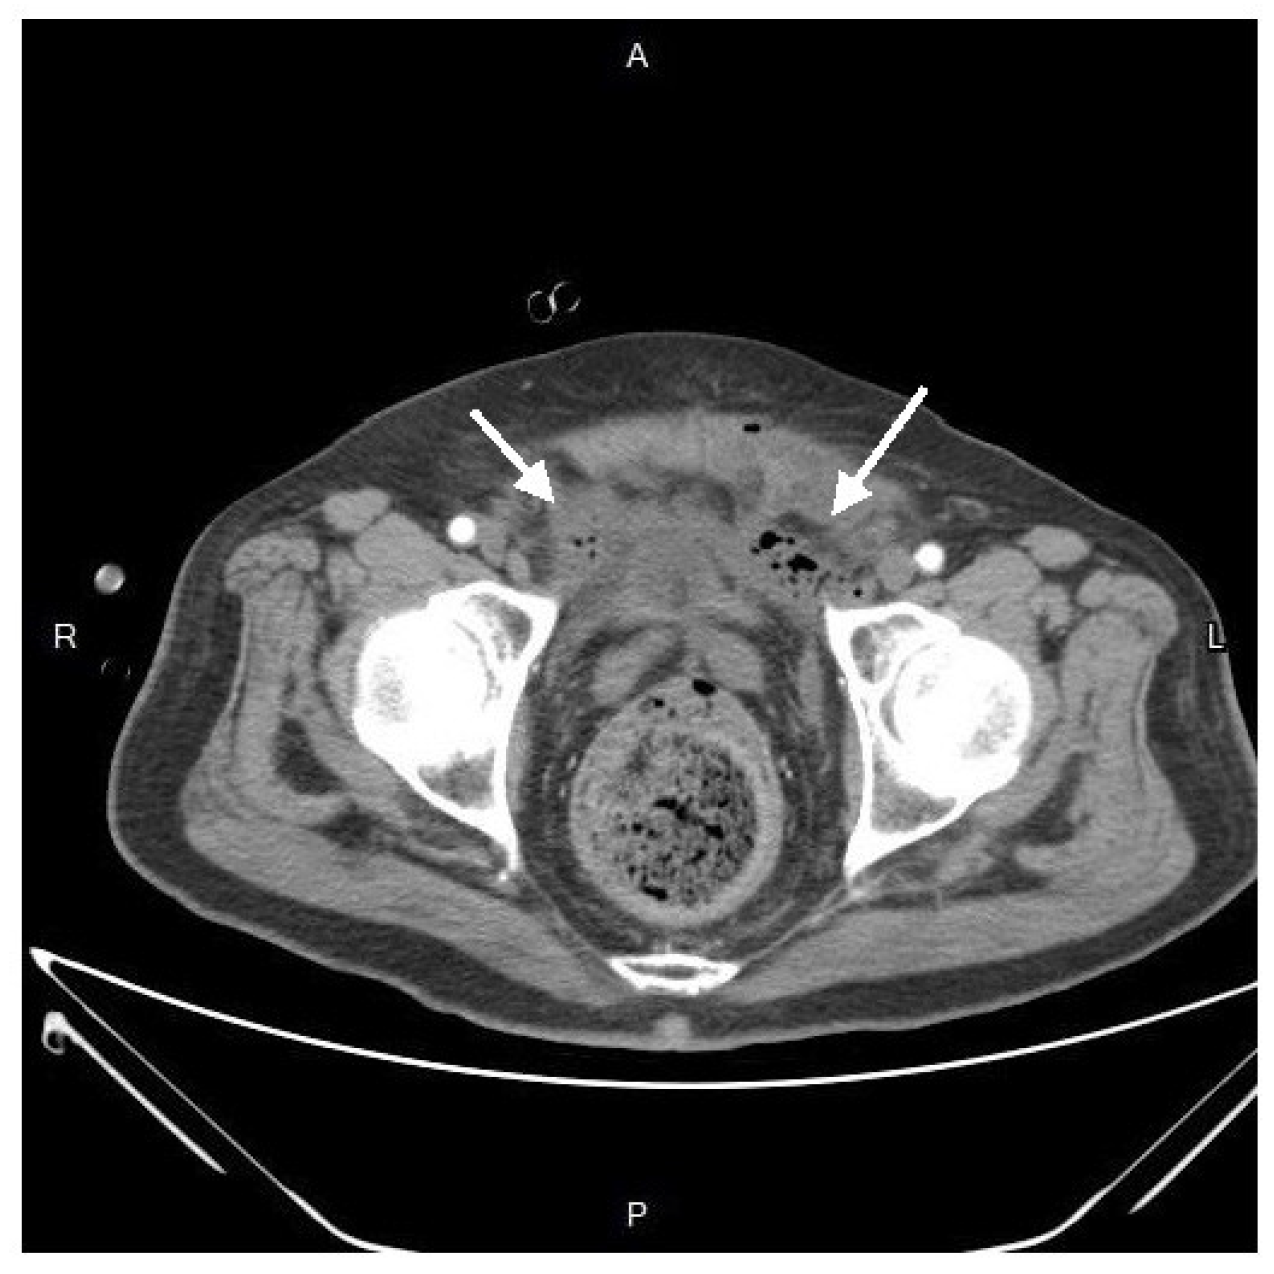

The blood cultures were drawn, and broad-spectrum empiric antibiotics were initiated. Following fluid resuscitation, the patient underwent incision and drainage in the 8 o’clock region, with the placement of a Foley tube for adequate drainage and irrigation. Subsequent dressing changes were performed regularly for proper hygiene. However, ten days later, the patient experienced sudden massive rectal bleeding with hypovolemic shock. Upon examination with an anal retractor, a bleeder was identified at the rectum in the 9 o’clock region, successfully managed by suturing ligation with 2-0 Vicryl. An emergent colonoscopy revealed no active bleeding or rectal ulcers. Simultaneously, an emergent abdomen and pelvic CT indicated no contrast medium extravasation in the bowel lumen or peritoneal space but identified an extraperitoneal abscess around the bladder.

After resuscitation and blood transfusion, his vital signs stabilized, and the inotrope was tapered. Upon the next day, we consulted a radiologist for CT-guided extraperitoneal abscess drainage, (Figure 4) collecting a considerable amount of turbid fluid. Cultures from the pus identified Klebsiella pneumoniae, Escherichia coli, Viridans streptococcus gr., and Bacteroides fragilis.

Figure 3. Sagittal view in contrast-enhanced computed tomography. The migration seemed to originate from the perianal region to the supralevator plane, and the preperitoneal space(arrow).